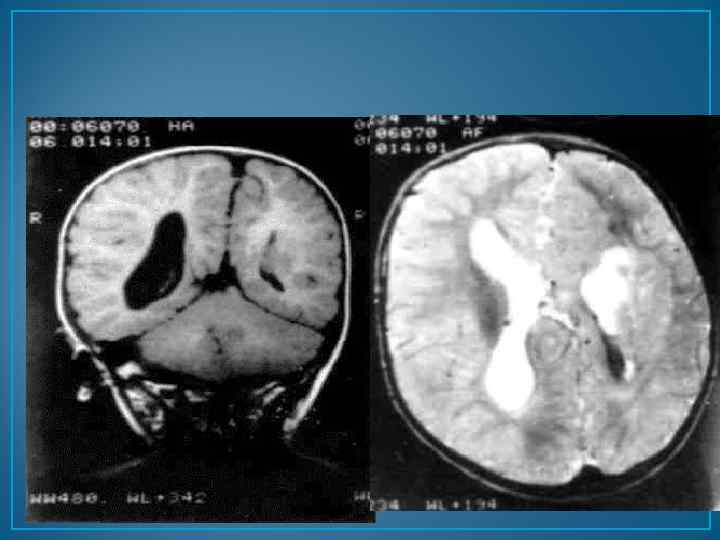

МРТ головного мозга